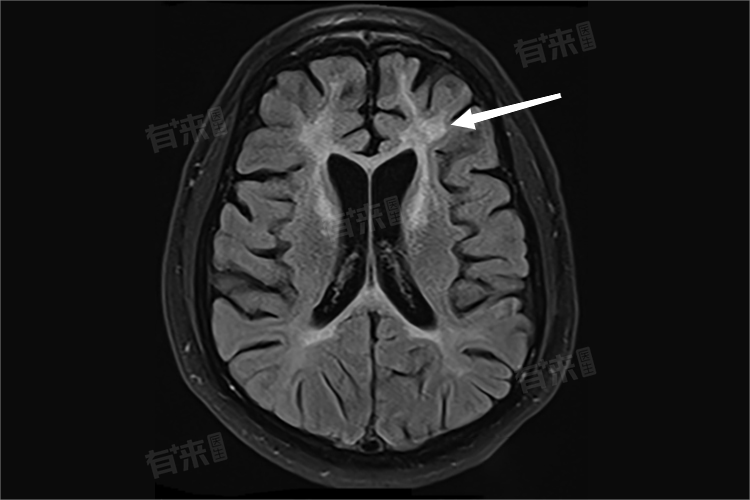

脑白质脱髓鞘病变是一种神经系统疾病,指的是脑白质中的神经纤维髓鞘发生变性或丧失,可能较为严重,应积极给予正确措施处理。患者应及时就医,明确病因,并在医生的指导下进行治疗。

- 脑白质脱髓鞘病变可以由多种原因引起,包括自身免疫性疾病、感染、中毒、退行性变、外伤后等。当上述因素导致中枢神经系统损伤时,会引发一系列炎症反应,包括巨噬细胞浸润、胶质细胞增生以及血管内皮细胞受损,最终导致神经纤维的髓鞘破坏,影响神经信号的传导。

- 脑白质脱髓鞘病变的严重程度因个体差异而异,主要取决于病变的范围、病因以及患者的年龄、健康状况等因素。一般来说,如果病变范围较小,且患者年龄较轻、健康状况良好,病情可能相对较轻,甚至可能没有明显的临床症状。

然而,如果病变范围广泛,或患者年龄较大、伴有其他慢性疾病,病情可能较为严重,患者可能会出现明显的临床症状,如认知障碍、记忆力减退、注意力不集中、运动协调能力下降、步态异常、肌张力增高、尿失禁等。